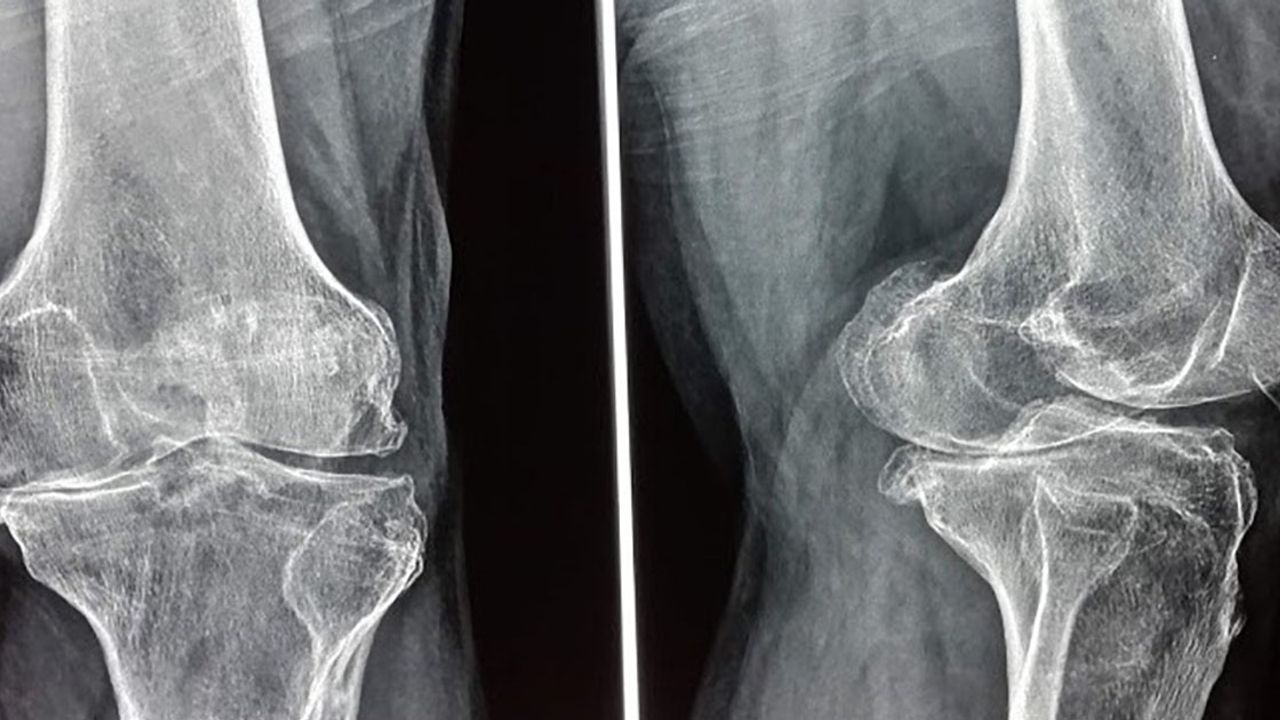

• röntgende ileri kıkırdak kaybı